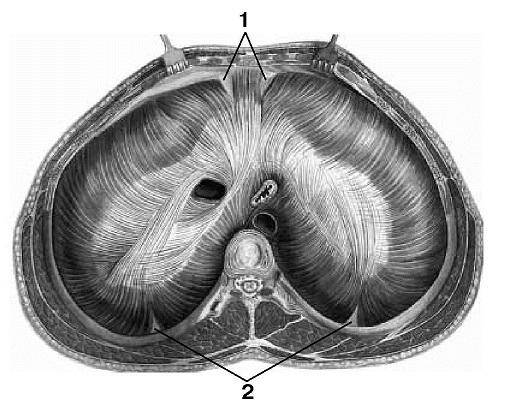

Анатомия диафрагмы и треугольника Бохдалека